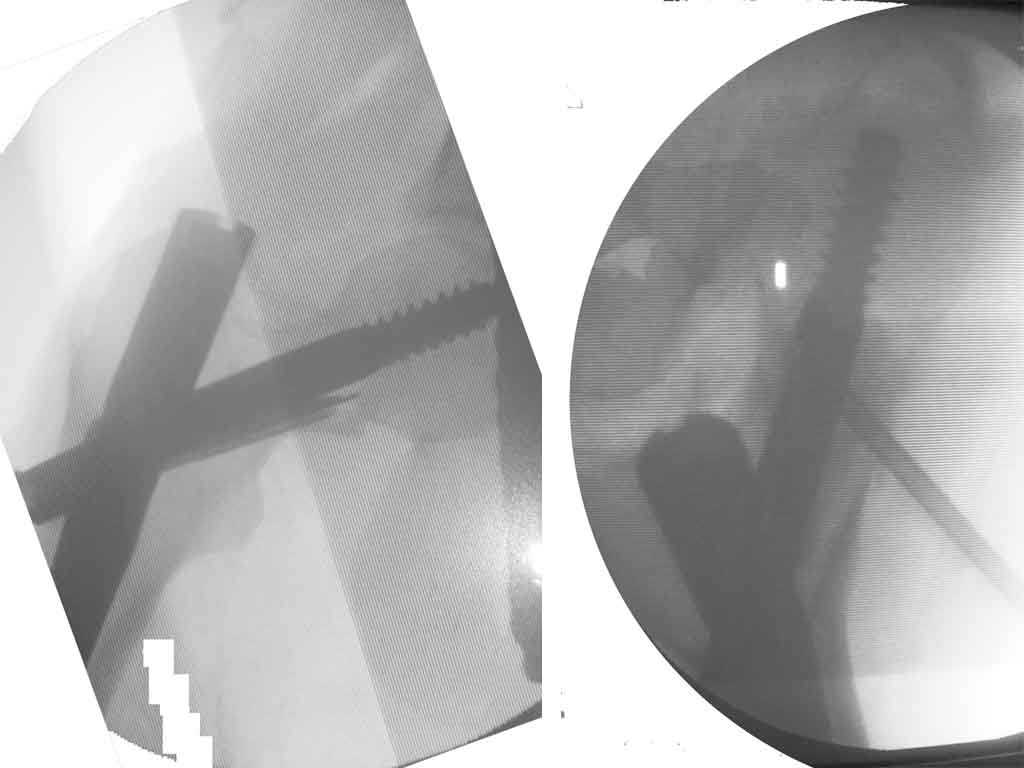

Приносим извинения за молчание. Больная прооперирована: под контролем ЭОП (защита плода несколькими халатами) выполнена закрытая репозиция на ортопедическом столе и фиксация Stryker Gamma 3 nail. Послеоперационные рентгенограммы мы решили не делать, чтобы не давать и без того чрезмерную нагрузку на плод. Поэтому придется довольствоваться картинкой с ЭОПа, правда сделанную на неподходящий для таких условий съемки фотоаппарат.

Да, забыли добавить, что во время оперции взят материал на гистологическое исследование (результат еще не получен) и в полость инъецирован жидкий OSTEOSET® (видно на аксиальной проекции). Металлокнструкции, которые видны на рентгенограммах - это те проводники, по которым вводился в полость OSTEOSET®.